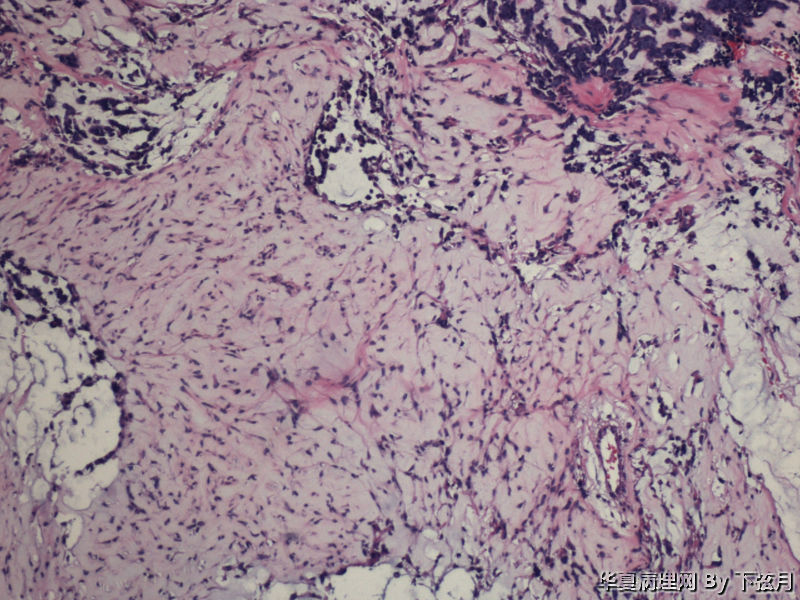

左侧颞叶及胼胝体膝部占位图2

名称:图2

描述:HE 100倍

有血管轴乳头,粘液样物中漂浮的细胞呈团块状和小乳头状。支持粘液型乳头状室管膜瘤。

考虑黏液型乳头状室管膜瘤

丰富黏液背景,漂浮乳头状或簇状分布的瘤细胞,免疫组化GFAP,S-100阳性。

This enhancing lesion with GFAP positive cells and should consider some type of glioma, probably high-grade.

But some cells in fig 7 and 8 are worrisome, need to rule out other type tumors, like chordoma. Other small round blue cell tumors.